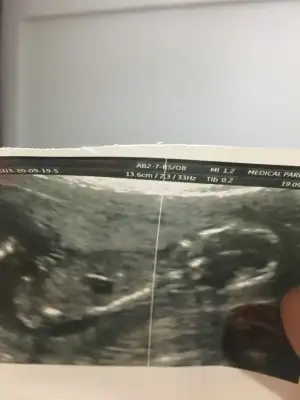

Bence erkek :))Merhabalar arkadaşımın bebeği 11+3 te tahmin eder misiniz çok merak ediyoruzIkra meyra

Eki Görüntüle 2694972

Erkek gibi ama siz yine USG olursa paylasinMerhabalar arkadaşımın bebeği 11+3 te tahmin eder misiniz çok merak ediyoruzIkra meyra

Eki Görüntüle 2694972